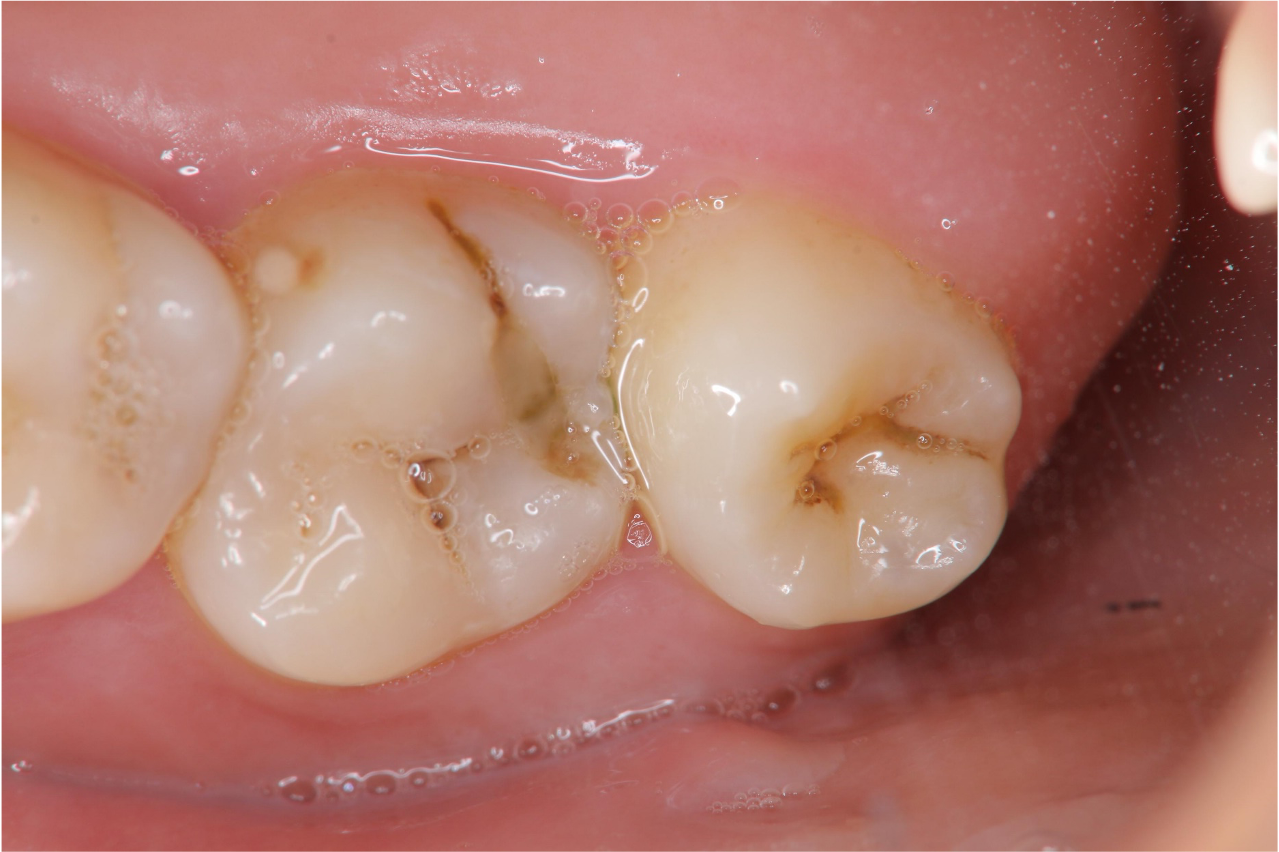

治療前,左上阻生齒為過度萌出,容易卡食物蛀牙

治療前,環口X光,深度蛀牙